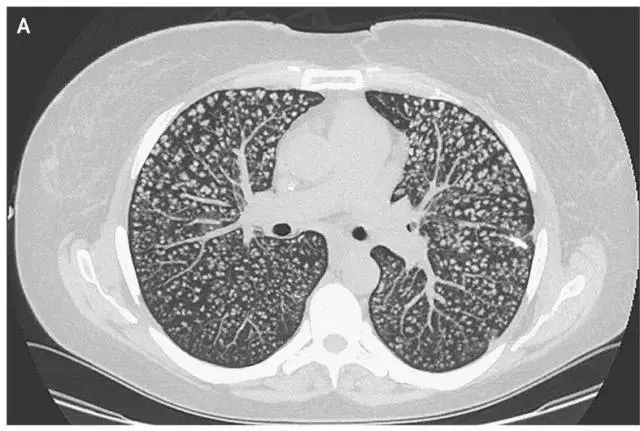

结核性肉芽肿结节的影像特点和鉴别诊断

图片尺寸1080x811